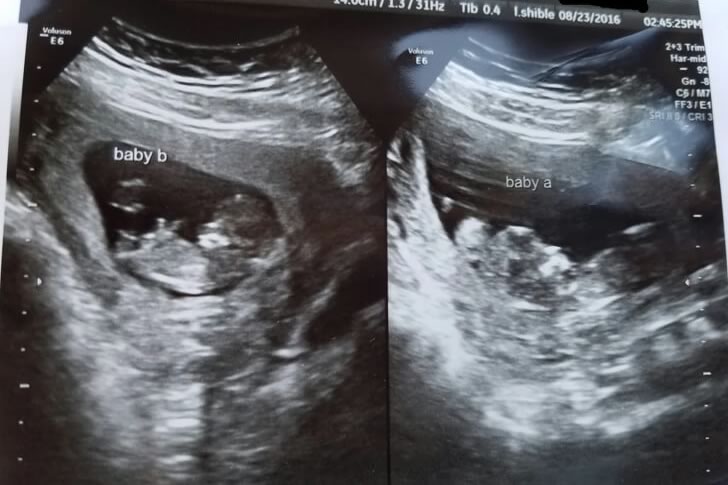

Lilly and Pradeep were filled with disbelief and excitement when the pregnancy test revealed not just one, but two babies on the way. For years, they had dreamed of becoming parents, and now that dream was coming true—twice over. Their hearts raced with joy, but in the background loomed the intimidating thought of raising twins. They knew their world was about to be flipped upside down.